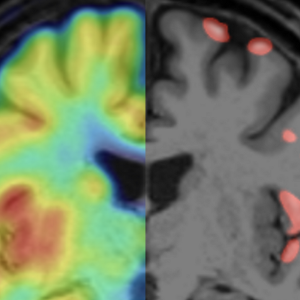

Multiple Sklerose: Nachweis veränderter grauer Substanz mittels PETRund 250.000 Menschen in Deutschland leiden an Multipler Sklerose (MS). Forschende der LMU haben nun erstmals gezeigt, dass sich mit PET-Aufnahmen der Synapsenverlust im Gehirn sichtbar machen lässt – ein möglicher Schritt zu gezielterer MS-Therapie.